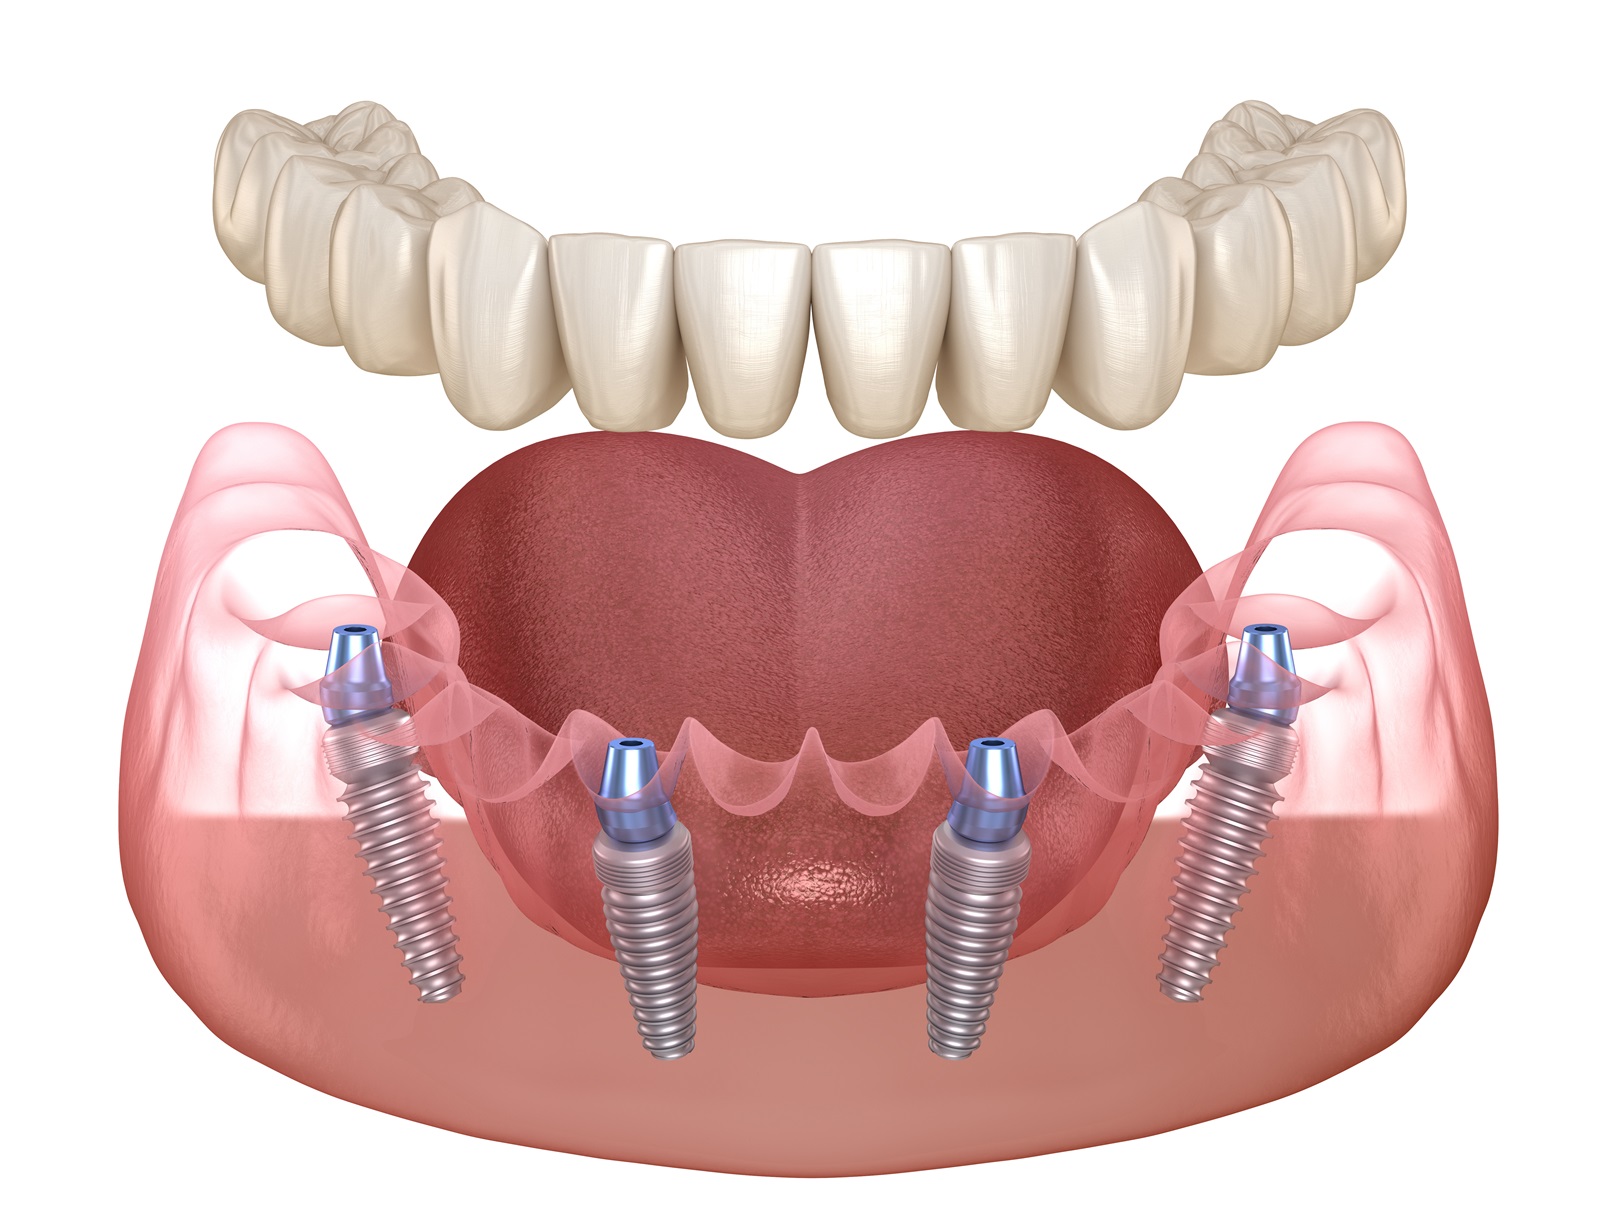

4本のインプラントですべての歯が入るAll-on-4に対応

失った歯の本数だけインプラントを入れようとすると、負担に感じる方が多いのではないでしょうか。そこで行っているのがAll-on-4(オールオンフォー)です。片顎につき最小4本のインプラントですべての歯を支えることができます